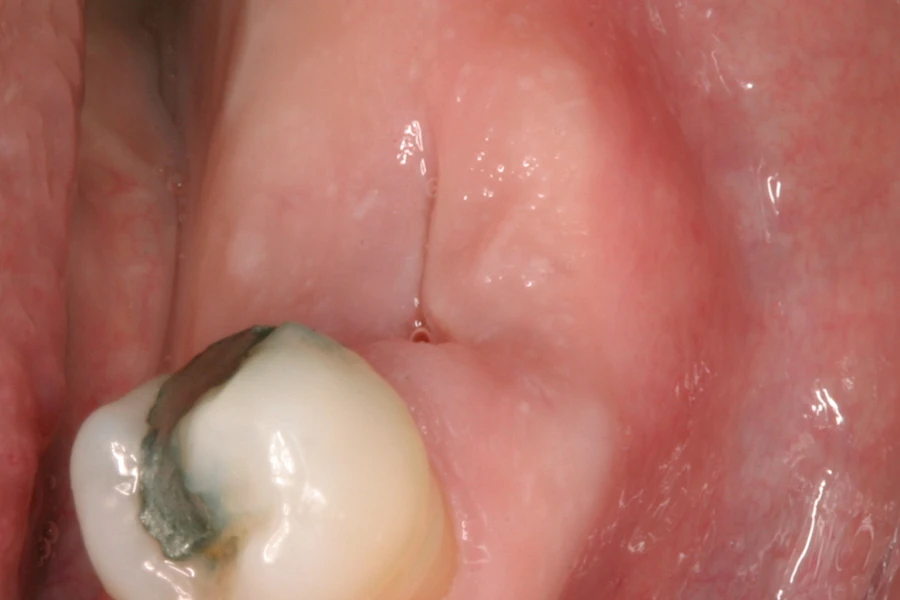

- 抜歯窩治癒の最適化

- 抜歯窩にPRGFクロットを填入することで、出血・腫脹・ドライソケットを抑制し、骨再生や軟組織の治癒を促進します。